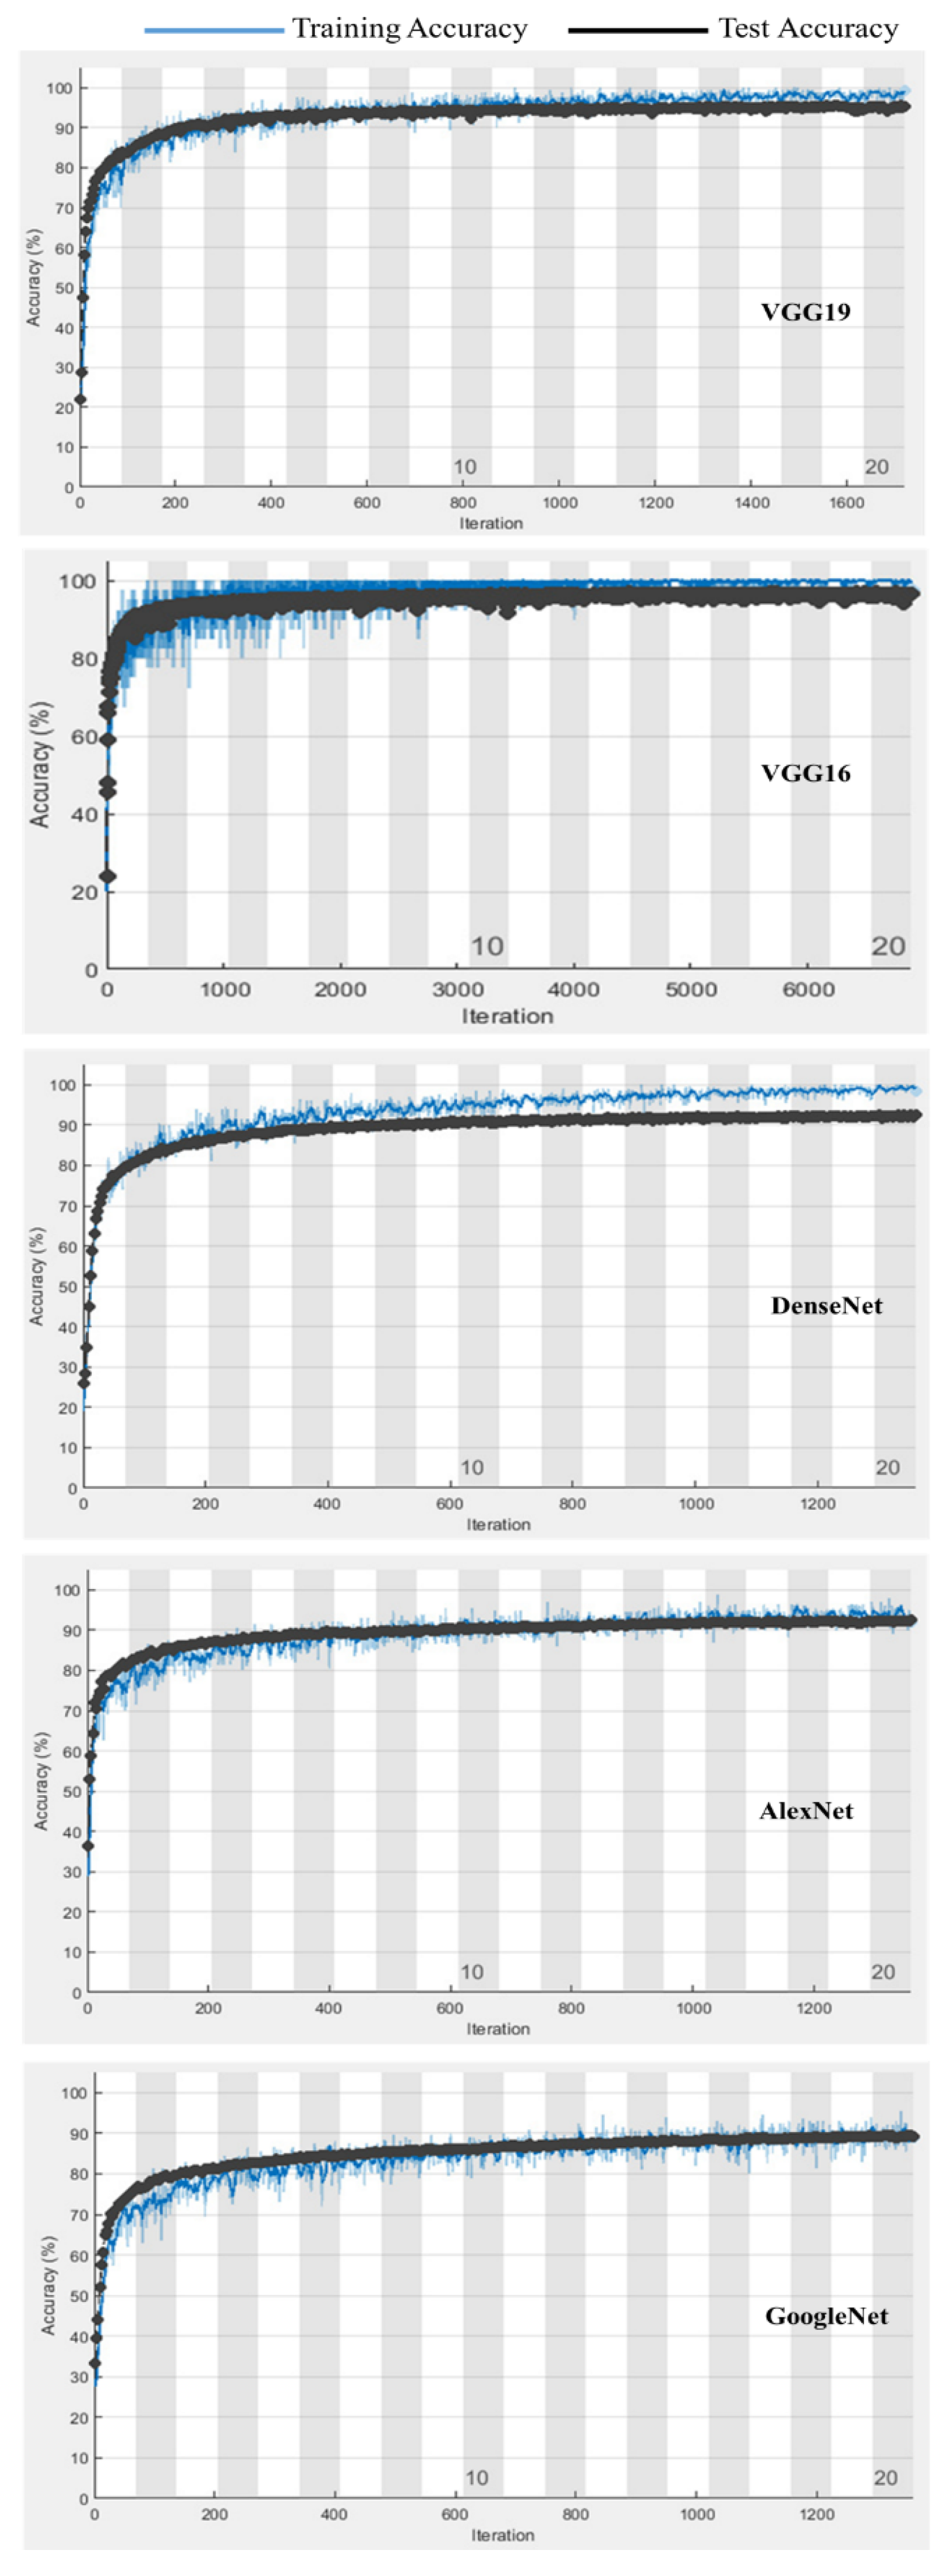

Figure 7 shows a comparison for the training and testing validation accuracies for the enhanced augmented normalized data for the different deep learning models. The results for the transfer learning-based VGG16 model indicate that the overfitting and underfitting problems were accounted for in this research, with no underfitting or overfitting problems reported.